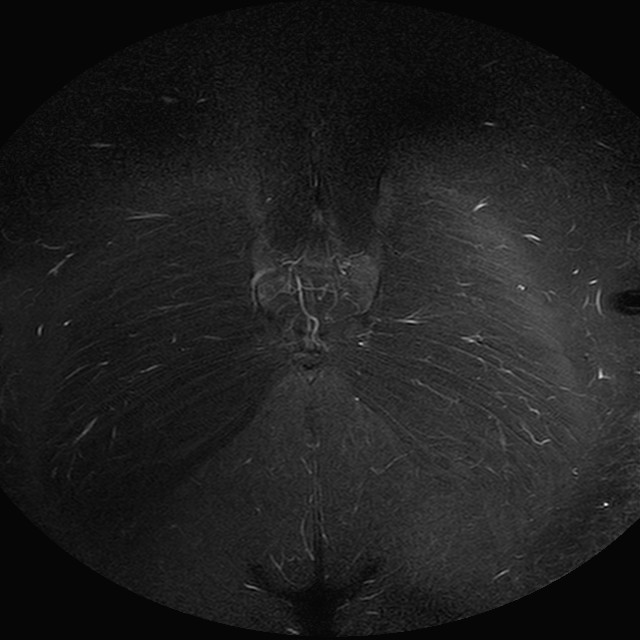

Esami: RMN BACINO

eSTIR

Evidenti e simmetriche alterazioni osteofitosiche in regione coxo femorale con riduzione delle rime articolari. Degenerazione completa del cercine glenoideo. Non attuali segni di versamento articolare. Non segni di edema osseo che escludono attuale algodistrofia od osteonecrosi. Lieve e simmetrica riduzione del trofismo della muscolatura glutea.